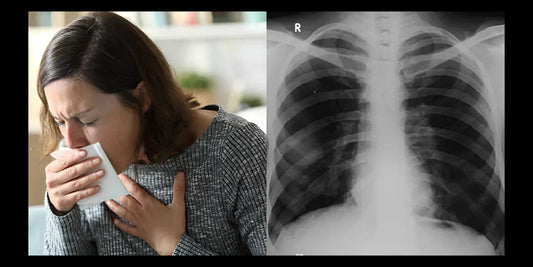

You've been coughing for months. That dry, persistent cough that won't quit. It's not a cold. It's not seasonal. You're not sick. But you can't stop coughing.

Taking Blood Pressure Pills And Have A Persistent Dry Cough? This Isn't Allergies - It's A Side Effect Affecting 8 Million Americans. Here's What Actually Helps.

Your doctor said you have two choices: Switch medications and risk your blood pressure control, or "just live with it." But there's a third option they don't know about.